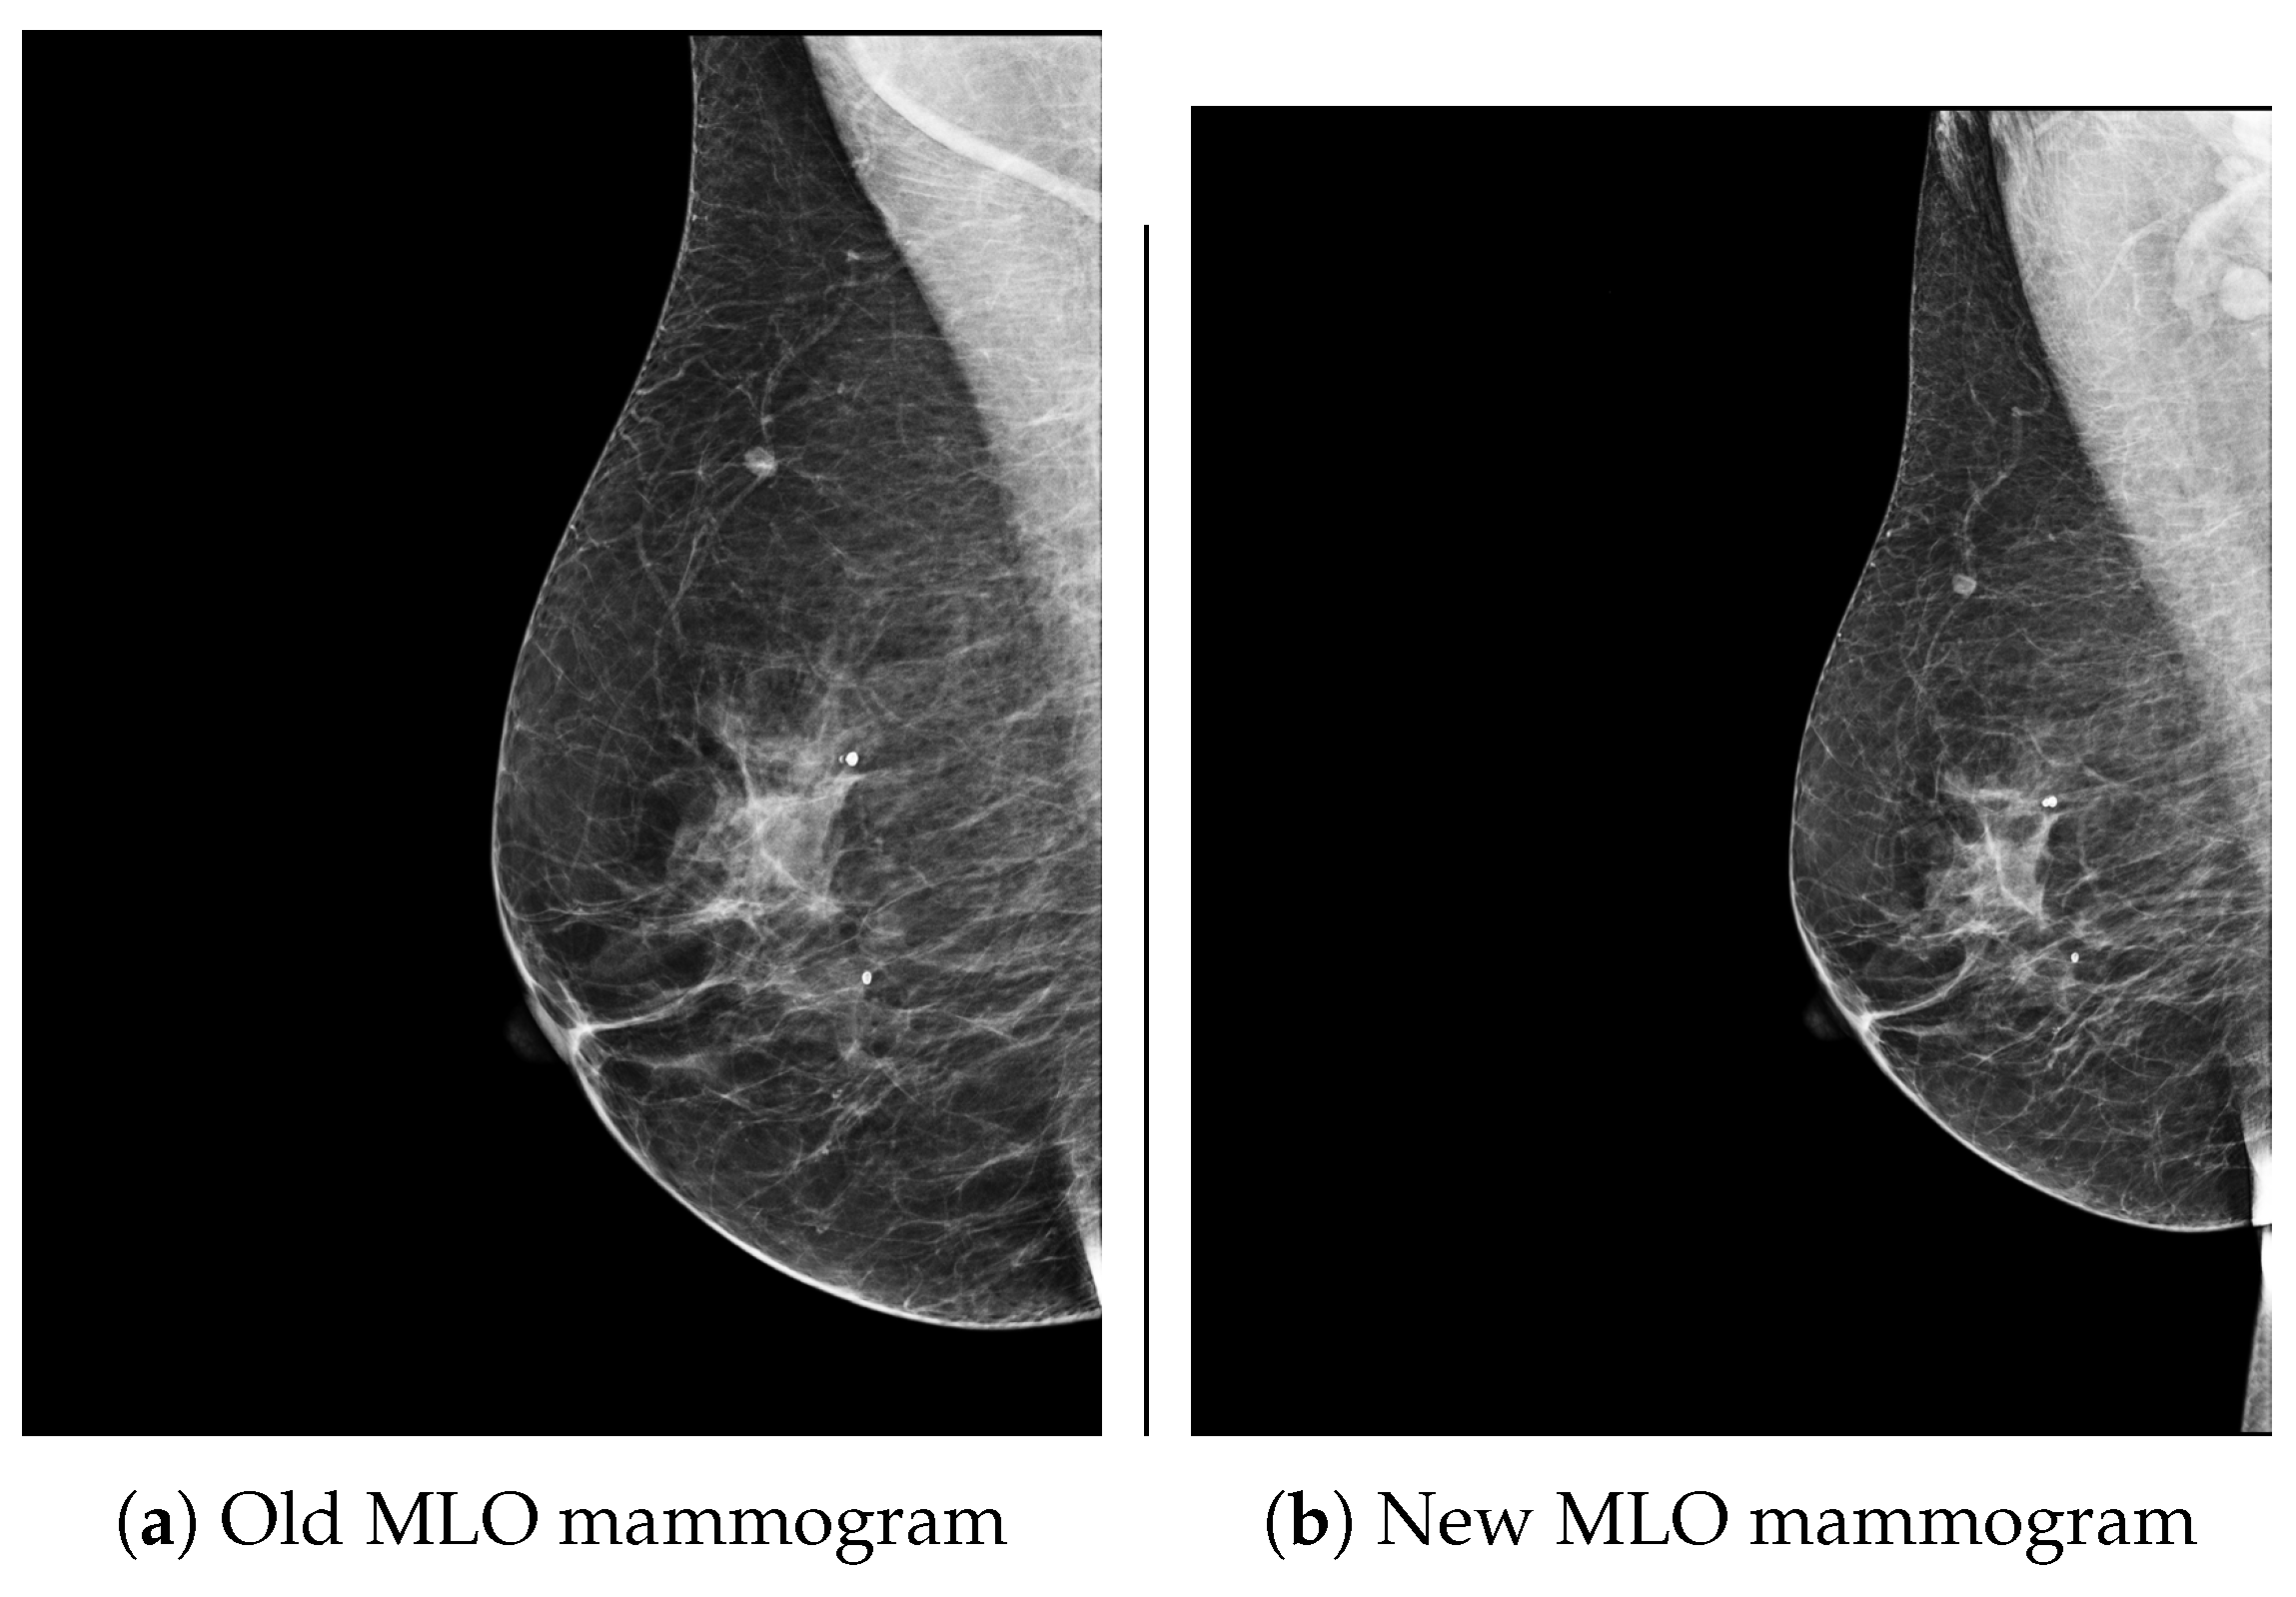

To address this issue, deformable or non-rigid registration algorithms are applied after global registration. At this stage, non-rigid registration becomes essential. In Figure 5, old and new MLO mammograms of the same patient are displayed.

With the MATLAB R2025a image registration tool, we apply image registration algorithms to these mammograms. We select an old mammogram as a reference image and make a new mammogram that overlaps/registers with the old one.

As seen in the Figure 5, the breast tissue of the new mammogram is smaller than that of the old one. Global geometric transformations can handle this, but breast tissue boundaries are not exactly the same. This means that during mammogram acquisition, the breast is compressed, and positioned angles are different between the two mammograms, and this causes shape distortions. Then, deformable (non-rigid) registration methods must be applied. As seen in Figure 6, after global geometric transformations, to overlap the new mammogram over the old mammogram, the demons [25,26] and B-spline FFD [27] algorithms are applied.

Figure 5. Two mammogram of the same patient. On the left side, the old mammogram, and on the right side, the new mammogram.